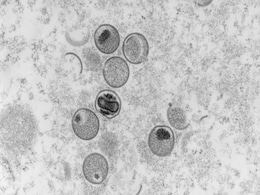

Monkeypox New Case In Delhi: मंकीपॉक्स वायरस एक मानव चेचक के समान एक दुर्लभ वायरल संक्रमण है. दिल्ली का मामला, पश्चिमी दिल्ली के पश्चिम विहार के एक 34 वर्षीय व्यक्ति में सामने आया है.